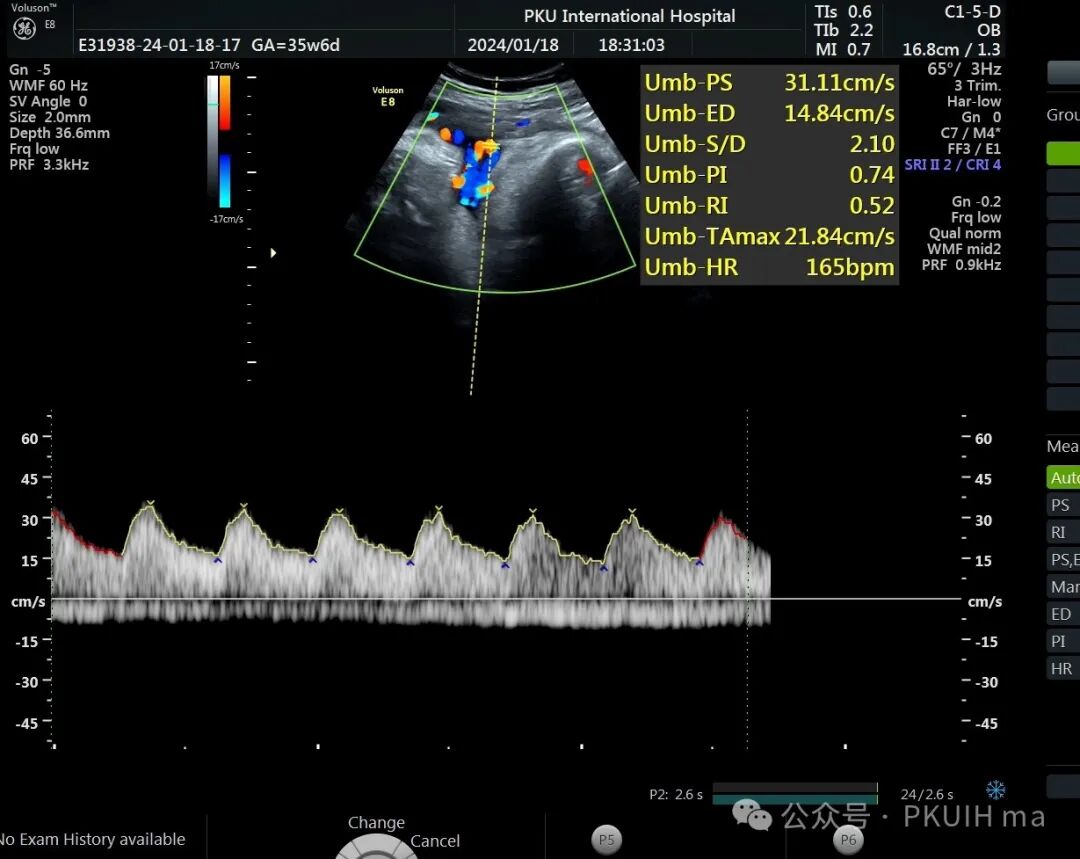

前两天碰到一孕妇胎动减少来诊,孕妇自述下午两点开始发现胎儿无明显胎动,吃了甜的食物和改变姿势还是不怎么动,随于下午六点左右来诊。超声发现胎儿绕颈两周以上且绕的较紧,检查中发现胎儿心率快,胎儿无明显胎动,绕颈处脐动脉血流加速时间延长,胎儿大脑中动脉阻力低,反复测量两侧大脑中动脉阻力均低。胎心监护也不好,随后产科采取紧急剖宫产。

脐带绕颈两周以上,绕的特别紧,感觉脖子都被勒细了,脐带与皮肤之间无任何空隙。绕颈处血流加速时间延长,说明可能存在交锁并出现了脐动脉局部狭窄